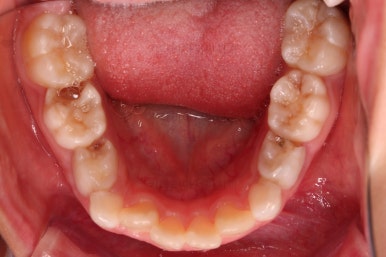

부산어린이반대교합 초진 시, 치열의 모습이에요.

우선 유치들이 많이 썩어서 치료가 필요해 보였고요.

앞니가 거꾸로 물려있고(아래 앞니가 위 앞니보다 앞으로 튀어나간 상황) 삐뚤어 있어요.